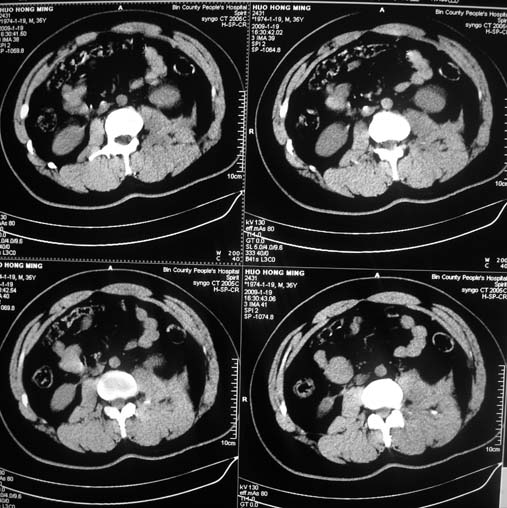

以下是引用余辉在2009-1-20 8:22:00的发言:[br]右侧肾上腺明显增大、边缘不光整,肯定有问题,结合患者病史考虑肾上腺挫伤、伴血肿形成。[br]另左肾后唇包膜下方可见局限性新月形高密度影,考虑肾包膜下出血[br]余同意楼上,建议增强排除脾破列

以下是引用随光逐影在2009-1-20 8:21:00的发言:[br]1)左侧多发肋骨及部分腰椎左侧横突骨折。2)左侧肾旁后间隙及同侧胸腔积血。3)左侧腰大肌肿胀。